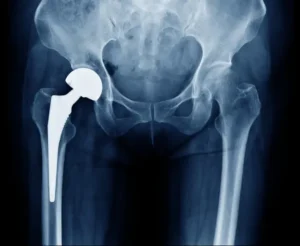

Experimentar dolor y limitaciones en actividades diarias debido al desgaste del cartílago de la cadera es ahora un desafío superable con la revolucionaria cirugía de reemplazo de cadera. Para aquellos cuya calidad de vida se ve afectada, esta intervención segura y eficaz no solo alivia el dolor, sino que también restaura el movimiento, permitiéndole disfrutar nuevamente de actividades antes limitadas.

El reemplazo de cadera puede estar inidcado en patologias como artrosis de cadera, fracturas por trauma o patológicas, condiciones congenitas entre otras.

La mayoría de los pacientes logran regresar a sus actividades a las 6 semanas y a los 3 meses ya recuperaron su fuerza y movilidad. Más del 80% de los casos tendrán una duración de 20 años funcional de la prótesis